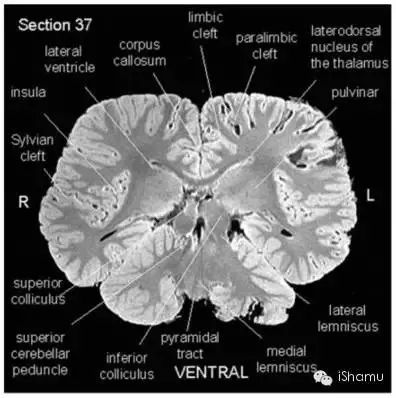

另外有一篇文献:“Neuroanatomy of the Killer Whale (Orcinus orca) From Magnetic Resonance Images”, 由神经生物学家Lori Marino et. al.于2004发表。该研究小组利用核磁共振成像技术,获得了宝贵的虎鲸脑部结构的图片。截了几张figure举几个栗子:

(Lori Marino et. al., 2004)

有医学背景的侠客朋友也应该看出来了。虎鲸的脑部解剖结构和人类脑部结构惊人的相似。同样有着高度折叠的大脑皮层沟回,有着形态和位置上高度相似的脑区(例如皮层,小脑,脑干,基底神经节),而且他们控制认知和情感的重要脑区Frontal lobe和Basal Ganglia也非常发达,同时也有着相对发达的参与记忆形成和学习的Limbic system包括著名的海马区,并且有着发达的Thalamus(丘脑)。